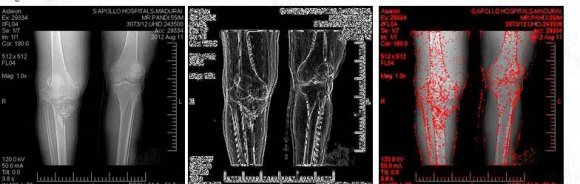

In the proposed work, two various types of image processing techniques are applied for the input (Big Data) as shown in the Fig. 3. The first technique is the combination Grayscale and Sobel edge detection. The second technique is the combination of Gaussian Blur and Fast Corner detection method. The Grayscale conversion is the best method to convert the original image into Black and White image and Sobel edge detection is the method of detecting the edges of the images.

Gaussian Blur is the best blurring technique ever, used here to blur the input image. Finally the Fast Corner Detection technique, since that is the best technique. After the completion of both the processing, the data is then transferred to the next level of Matching called SAD matching. Then the integration of the intermediate data is done to recognize the output.

The Harris corner detection is used in case when there is a correlation in the threshold of data. A detection method which could give a better result than the Harris corner is, Fast corner_9 which is shown in Fig. 4. Fast corner_9 has been applied in the proposed work, to fine tune the result than the Harris corner, Susan, zheng and harr [9] methods.

Fig 5 shows the result of the Fast Corner method. In this figure, the sharp edges and the damaged parts are pointed out sharply. The red mark shows the infected corners. When compared with the Harris corner method in the existing work [2], this is proved to be the best corner detection. The application of the two image processing techniques, gives the expected result. The main advantage during the execution was, the output of the data is marked with better quality and there is the usage of Fast corner_9 method to detect the corners of the image. While comparing with existing, proposed Fast corner_9 method shows the corner more clearly. During the comparison, it has been proved that, the method applied in the proposed algorithm works better than the existing. Whatever the size or format of images may be, the result will be produced in the pre defined format. The result occupies less space when compared with the size of the input for storing.